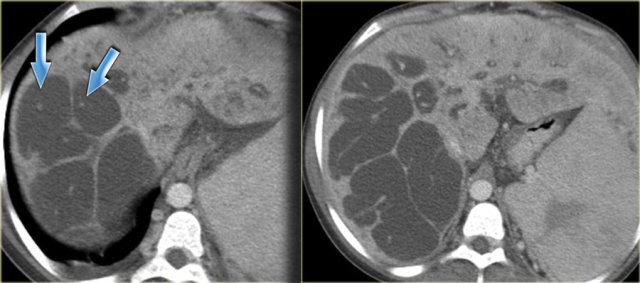

On the left we see images of a patient with Caroli disease.

Notice the intrahepatic duct dilatation and the normal caliber of the choledochal duct (extrahepatic bile duct).

The hallmark of Caroli disease is intrahepatic duct dilatation.

The dilatation can be very large and saccular as seen in the case on the left or it can be very linear.

On the left a patient with dilated bile ducts with intraductal stones (arrow)

Study the image on the left.

Then continue reading.

The findings are:

- Medullary sponge kidney with stone formation (red arrow)

- Mild bile duct dilatation (blue arrow)

- Round hypoattenuating mass in the right liver lobe

The mass in the right lobe of the liver turned out to be an abscess.

Remember that liver abscesses in the early phase can look quite solid.

In the differential diagnosis we would also have to include a neoplasm, because patients with Caroli disease have an increased risk of developing a cholangiocarcinoma.